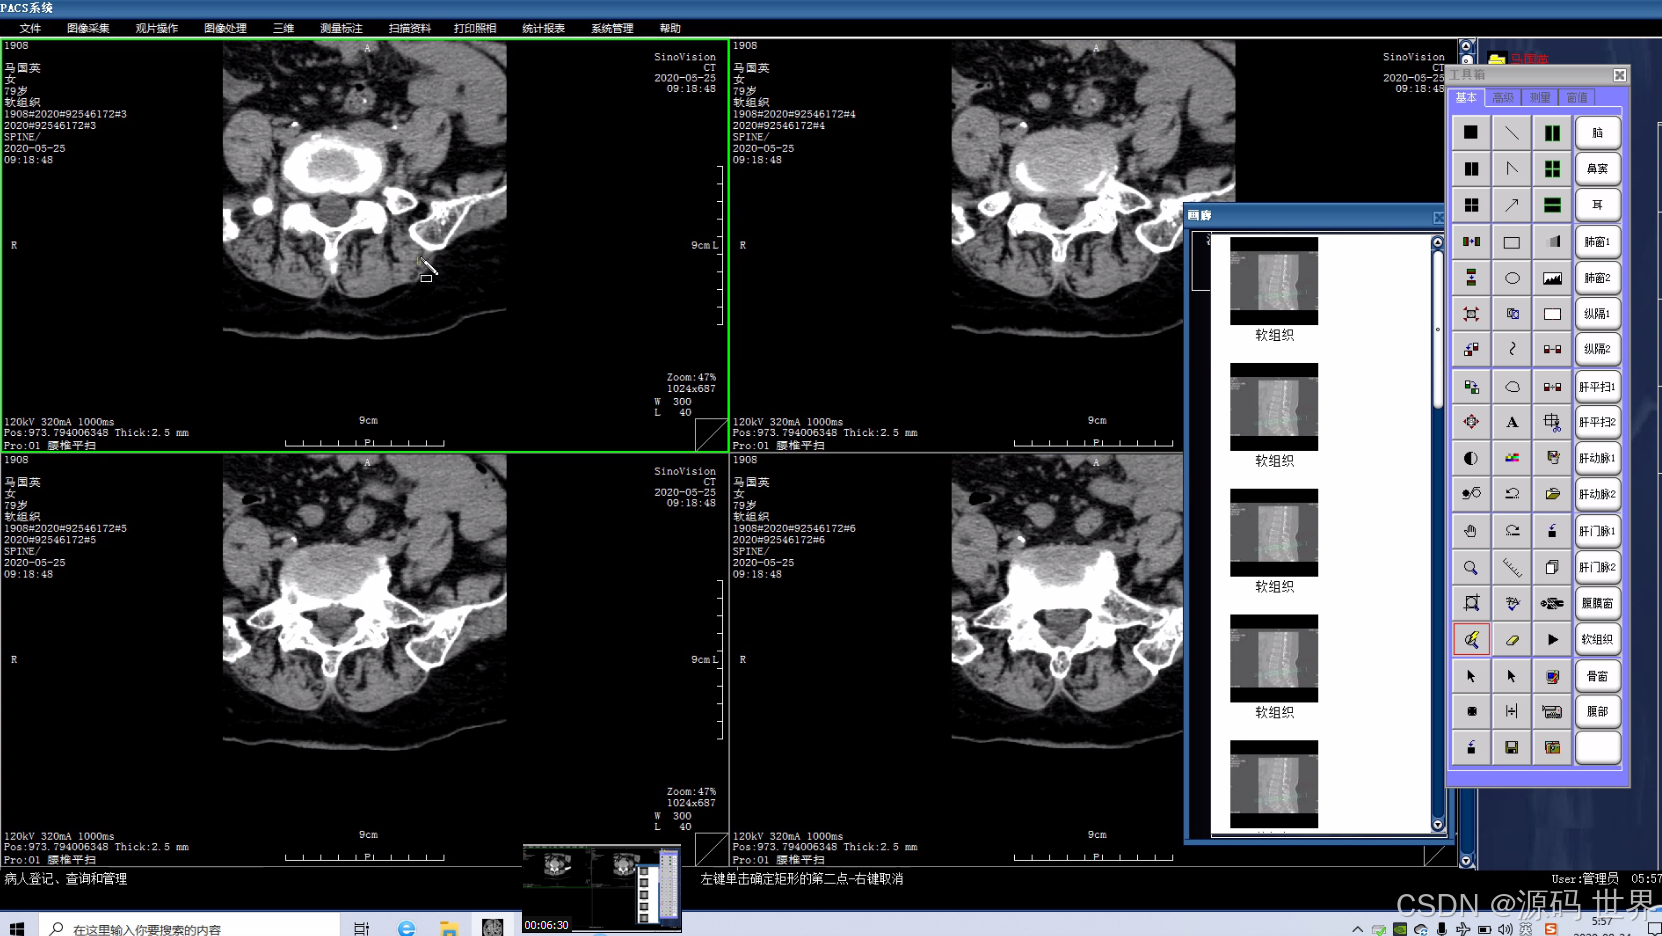

主要的任务就是把医院影像科日常产生的各种医学影像(包括核磁、CT、DR、超声、各种X光机等设备产生的图像)通过DICOM3、0国际标准接口(中国市场大多为模拟,DICOM,网络等接口)以数字化的方式海量保存起来,当需要的时候在一定的授权下能够很快的调回使用,同时增加一些辅助诊断管理功能。

1、影像设备:如X光机、CT、MRI、超声等医疗设备,用来产生医疗影像。

5、影像工作站:用于医生和专业技术人员查看、诊断、分析及操作影像的计算机和软件系统。